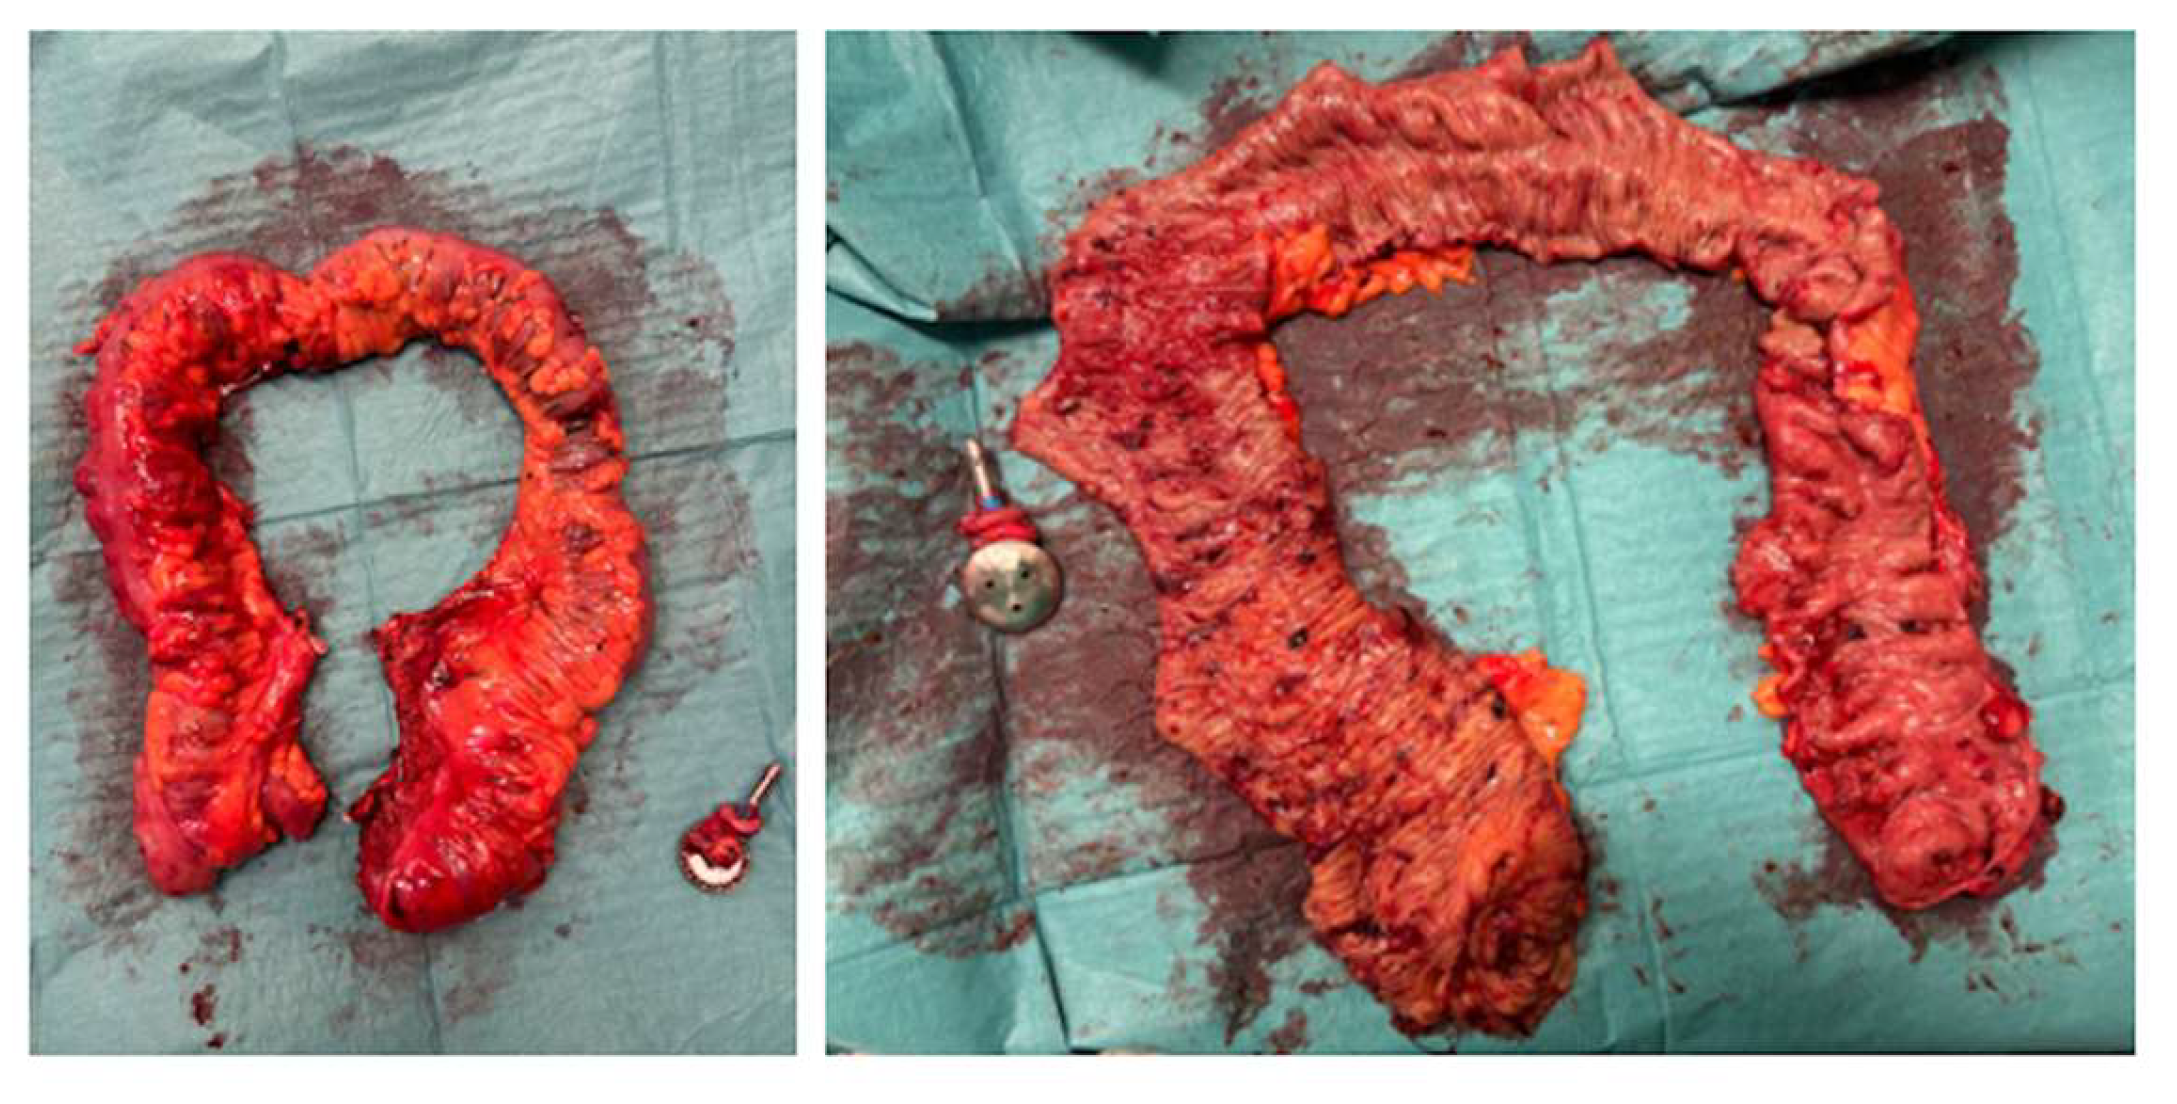

- Extraction of the surgical specimen.

- Ileorectal anastomosis